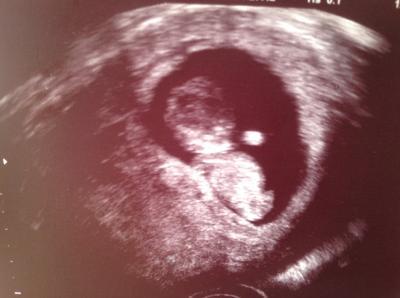

Bin heute beim FA gewesen. Dem Krümel gehts gut, er ist auf 4,1cm gewachsen. Bin heute von 10+2 auf 11+1 korrigiert wurden. Meine Ärztin hat den Ultraschall noch Vaginal gemacht, aber grade so. Der Krümel ist ziemlich groß, deshalb haben die Beine nicht mit aufs Foto gepasst.:-))) Die Nackenfaltenmessung in 14 Tagen muss durch die Bauchdecke gemacht werden. Nur den Geburtstermin hat sie nicht geändert. Muss ich beim nächstenmal nachfragen ob das auch geändert wird. Bekommt ihr von euren Arbeitgebern für die Untersuchungen frei? Ich habe keine Ü-Stunden mehr. Aber meine FÄ kann mir nur vormittags Termine geben. Wie ich das die nächsten Wochen hinbekomme weiß ich noch nicht?!?!?!

Oh, ein schönes Bild